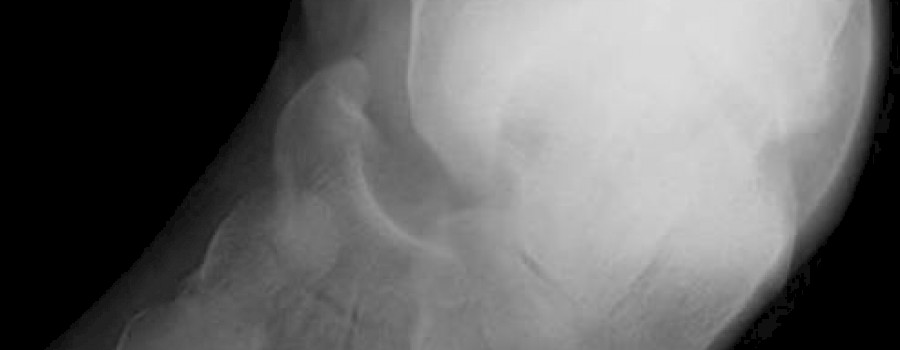

Die Röntgenassistentin im Jahre 1960

Als die technische Röntgenassistentin noch ein reiner Frauenberuf war....

Unbestritten ist das "Lehrbuch der röntgendiagnostischen Einstelltechnik" begründet von Marianne Zimmer-Brossy" ein Standardwerk, das auch heute noch in vielen Radiologischen Abteilungen verwendet wird.